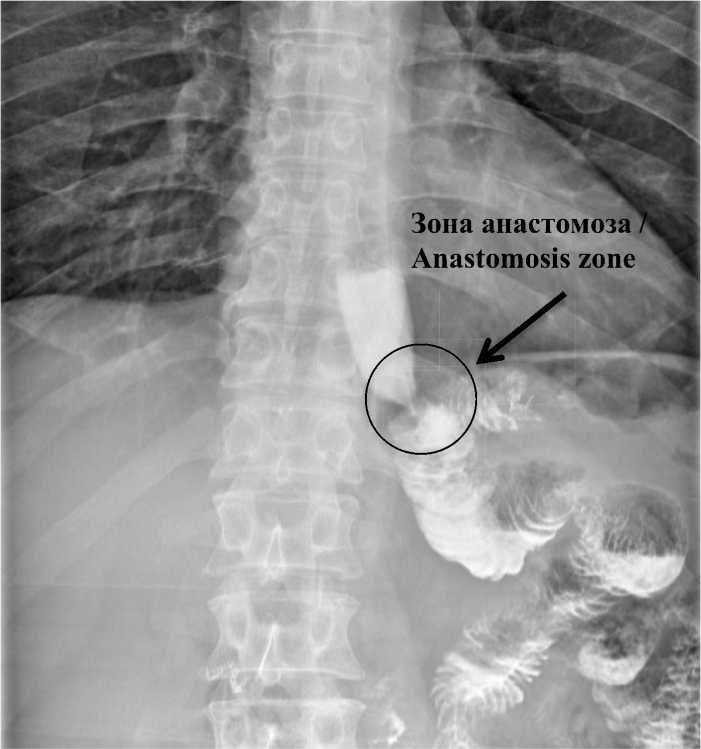

Дополнительно для оценки состоятельности и функционального статуса ЭЕА проведена рентгенография с водорастворимым контрастом на 7–10-е сут после оперативного лечения (рис. 9). В анализ было включено 35 пациентов.

Во всех случаях контрастная взвесь свободно проходила через анастомоз без задержек и признаков анастомозита. При повышении внутри-брюшного давления на вдохе рефлюкса контрастного вещества не отмечено.

Рис. 9. Рентгенография пациента на 8-е сут после оперативного лечения, Снимок сделан на вдохе

Fig. 9. Patient’s X-ray, postoperative day 8. The image was taken while inhaling